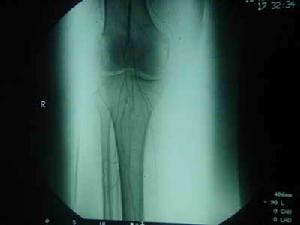

![FELTY綜合症[費爾蒂綜合徵] FELTY綜合症[費爾蒂綜合徵]](/img/7/33a/nBnauM3X2UTM1YjN4EDM5QjNyITMyYjN0YjMwADMwAzMxAzLxAzLzAzLt92YucmbvRWdo5Cd0FmLxE2LvoDc0RHa.jpg)